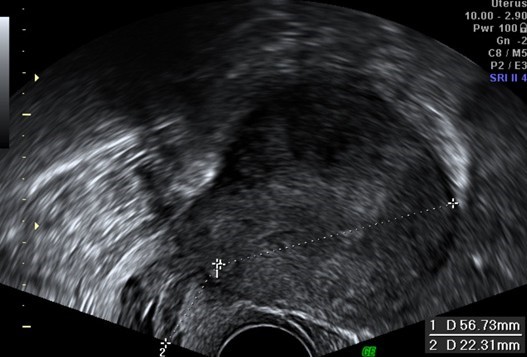

Immunohistochemical staining showed positivity for smooth-muscle actin, desmin and estrogen and progesterone receptors, while showing negativity for TTF1, AE1/AE3, bcl2 and CD34. The histological findings were compatible with BML (Figure 3). Due to these findings, the patient (who had no clinical history of known leiomyomas or other gynecological conditions) was referred to gynecological consultation and transvaginal ultrasound examination revealed a heterogeneous uterine wall with two intramural hypoechoic lesions (measuring 12 x 12 mm and 10 x 6 mm) and one subserosal hypoechoic lesion (measuring 54 x 28 mm), suggestive of uterine leiomyomas (Figure 4). The patient underwent hysterectomy and bilateral adnexectomy, and surgical histopathological study confirmed the diagnosis of multiple uterine leiomyomas, confirming the origin of the BML lesions found in the lungs. The latest postoperative CT chest scan for lung nodules evaluation showed overlapping characteristics, compared to previous imaging studies. As such, these BML lesions remain morphologically and numerically stable. The patient remained asymptomatic and was followed- up in consultation. No surgical or hormonal therapy was performed in regard to BML, and a CT chest scan was scheduled 6 months later to monitor the lesions.

Figure 4: Transvaginal ultrasound examination revealed a heterogeneous uterine wall with two intramural hypoechoic lesions (measuring 12 x 12 mm and 10 x 6 mm) and one subserosal hypoechoic lesion (measuring 54 x 28 mm), suggestive of uterine leiomyomas. Surgical histopathological study later confirmed this diagnosis.